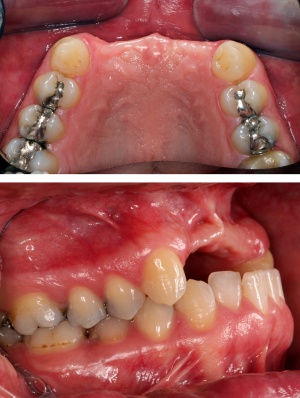

Im Oberkiefer konnten mit der Planungssoftware SkyPlanX der Firma Bredent 6 Implantate mit BoneSplit geplant werden (Abb. 2), im Unterkiefer war eine Implantation aufgrund ungenügenden Knochenangebots nicht möglich.

Im August 2012 erfolgten die 3D-gestützte Implantation (6 Implantate, Firma Nobel Biocare, System Active) im Oberkiefer mit Bone Split sowie eine An- und Auflagerungsosteoplastik vom linken Beckenkamm im Unterkiefer nach Entfernung der Miniimplantate (Abb. 3). Nach komplikationsloser Einheilung wurde im Dezember 2012 die Materialentfernung und Implantation im Unterkiefer (6 Implantate, Firma Nobel Biocare, System Active) durchgeführt (Abb. 4). Die Osseointegration verlief ungestört. Aufgrund der ungenügenden Weichgewebssituation im Unterkiefer erfolgte an jedem Implantat bei Freilegung eine Vestibulumplastik mit Einlagerung einer bioresorbierbaren Membran (Firma Botiss, Mucoderm, Abb. 5 und 6). Die endgültige prothetische Versorgung erfolgte durch den truppenzahnärztlichen Kollegen in der Stammeinheit des Patienten (Zahnarztgruppe Nordholz / SanZ Celle) mit einer gaumenfreien implantatgetragenen Teleskopprothese im Ober- und Unterkiefer, die eine festsitzend-herausnehmbare vollständige stomatognathe Rehabilitation des Patienten ermöglichte (Abb. 7 und 8). Er wurde zum halbjährlichen Recall angehalten.

Die Lücke war bis dato über eine insuffiziente Teilprothese versorgt. Es bestand eine ausgeprägte Oberkieferatrophie in allen Dimensionen mit negativer Stufe im Verhältnis Oberkiefer zu Unterkiefer (Bild) sowie Elongation der Unterkieferfrontzähne (Abb. 9).

Zum Ausgleich der konsekutiv vorliegenden Weichgewebsatrophie erfolgte im Juni 2012 nach Genehmigung des Antrags durch das Sanitätsamt der Bundeswehr zunächst die Implantation von 2 Weichgewebsexpandern (Firma Osmed) im Oberkiefer (Abb. 10). Nach Schaffung eines adäquaten Weichgewebsbettes wurde im Juli 2012 zur Korrektur der extremen Hartgewebsatrophie eine Augmentation vom Beckenkamm durchgeführt (Abb. 11). Im Dezember 2012 erfolgten in Lokalanästhesie nach ungestörter Einheilung die Materialentfernung der Osteosyntheseschrauben und die Implantation von 4 dentalen Implantaten (Firma Nobel Biocare, Replace straight, Abb. 12). Durch Atrophie und die rekonstruktiven Operationen bedingt, wurde zur Korrektur der ungenügenden Weichgewebsverhältnisse eine Vestibulumplastik nach 3 Monaten mit Einlagerung einer bioresorbierbaren Membran (Firma Botiss, Mucoderm) durchgeführt. Nach weiteren 3 Monaten erfolgte die Freilegung der Implantate (Abb. 13) mit einer Rolllappenplastik an jedem Implantat zur vestibulären Rekonturierung der Schleimhaut.